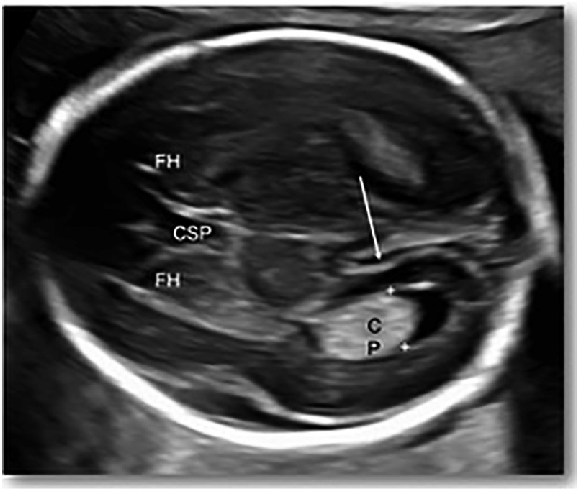

Projemizin içeriği, 2 boyutlu fetal beyin ultrasonografi (USG) görüntülerinde lateral ventrikül anomalilerinin yapay zekâ destekli olarak tespit edilmesine odaklanan, klinik gerçekliğe dayalı bir karar destek sistemi geliştirilmesini kapsamaktadır.

Proje, AI-Assisted Detection of Lateral Ventricular Abnormalities in 2D Fetal Brain Ultrasound başlığı altında, fetal nörosonografide sık karşılaşılan operatör bağımlılığı, yorumlama farklılıkları ve sınıf dengesizliği gibi temel problemlere çözüm üretmeyi amaçlayan anatomi odaklı bir proof-of-concept çalışma olarak tasarlanmıştır.

Çalışmada, 18–24 gebelik haftaları arasında rutin prenatal muayeneler sırasında elde edilmiş ve tamamen anonimleştirilmiş arşiv fetal beyin USG görüntüleri kullanılmıştır. Tüm görüntüler, ISUOG kılavuzlarına uygun transventriküler aksiyel planlardan elde edilmiş ve 15 yılı aşkın deneyime sahip bir fetal nörosonografi uzmanı tarafından “normal” ve “anormal” olarak etiketlenmiştir. Bu uzman etiketleri, model için altın standart (ground truth) olarak kabul edilmiştir.